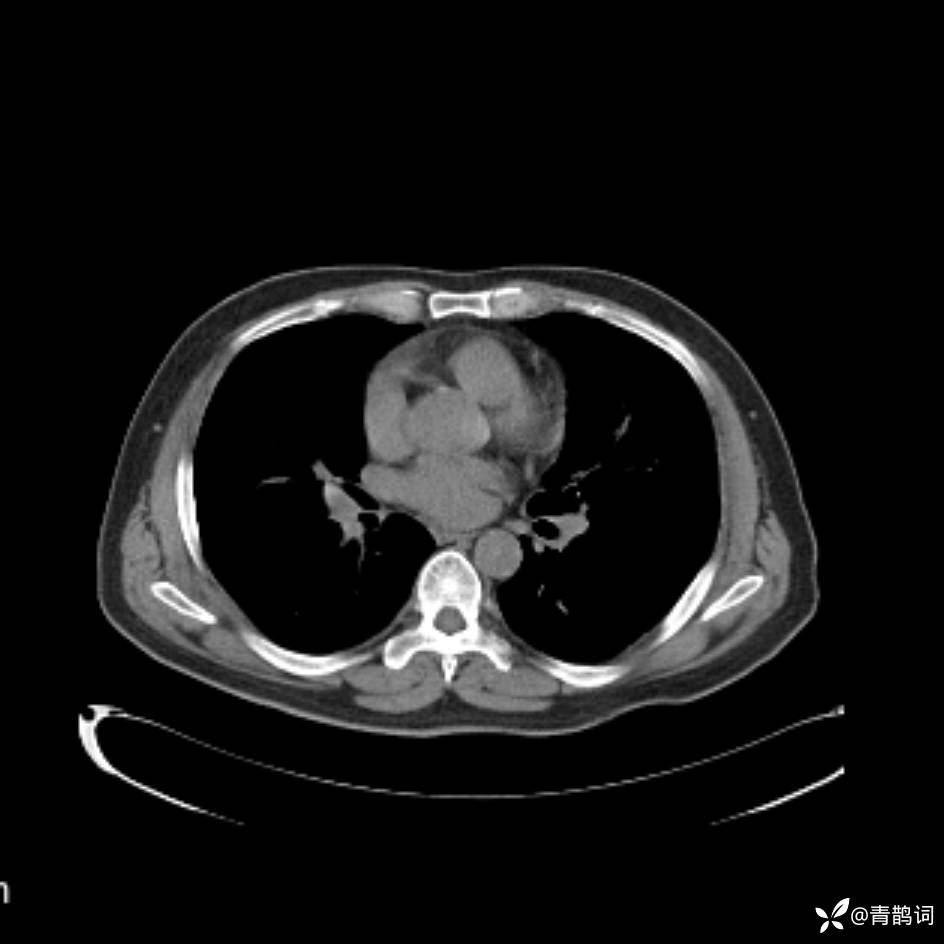

患者年龄:30岁。

患者性别:男。

简要病史:左颜面部肿胀2年,反复咳嗽咳痰,逐渐加重。

辅助检查

结合病史及影像学表现,期待评论区各位老师各抒己见~